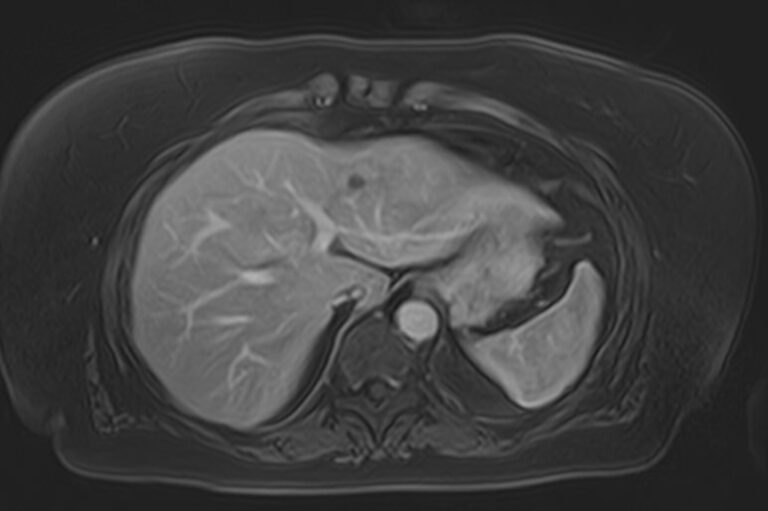

Магнитно-резонансная томография брюшной полости является наиболее информативной безопасной и эффективной методикой обследования внутренних органов. Метод позволяет проводить дифференциальную диагностику в сложных клинических случаях. Особенно это важно при противоречивых и неоднозначных данных, полученных при проведении УЗИ, рентгенографии, КТ или других обследованиях.

В клинике «Доступная медицина» МР томография проводится на новейшем высокопольном томографе экспертного класса TOSHIBA VANTAGE TITAN 1,5 Тесла. Высокая индукция магнитного поля обеспечивает повышенную четкость изображений при проведении обзорной МРТ брюшной полости, что гарантирует точность и эффективность диагностики заболеваний печени, желчного пузыря, поджелудочной железы и селезенки. Аппарат послойно сканирует исследуемую область с шагом от 1 мм в различных плоскостях, затем трансформирует результаты в трехмерные изображения превосходного качества. Для уточнения характера патологических изменений одного из органов назначается прицельная МР томография данного органа.